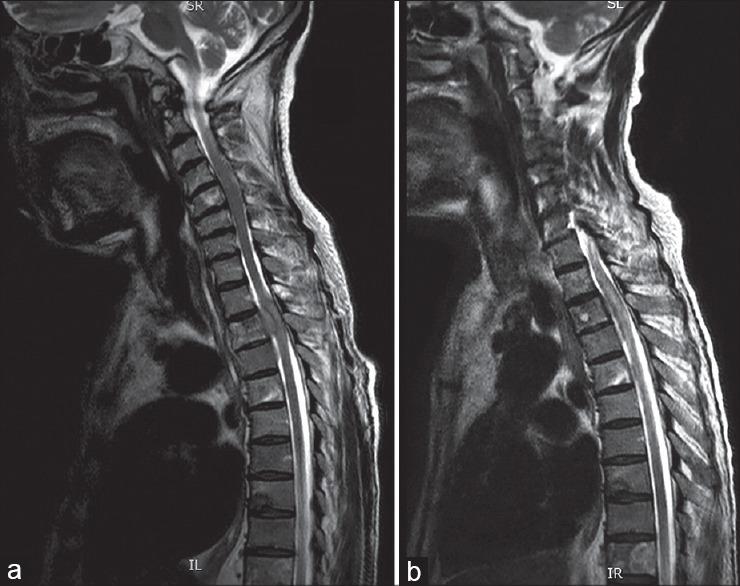

Skeletal metastasis is a common cause of severe morbidity, reduction in quality of life (QOL) and often early mortality. Its prevalence is rising due to a higher rate of diagnosis, better systemic treatment, longer lives with the disease and higher disease burden rate. As people with cancer live longer and with rising sensitivity of body imaging and surveillance, the incidence of pathological fracture, metastatic epidural cord compression is rising and constitutes a challenge for the orthopedic surgeon to maintain their QOL. Metastatic disease is no longer a death sentence condemning patients to "terminal care." In the era of multidisciplinary care and effective systemic targeted and nontargeted therapy, patient expectations of QOL, even during palliative end of care period is high. We lay emphasis on proving the diagnosis of metastasis by biopsy and histopathology and discuss imaging modalities to help estimate fracture risk and map disease extent. This article discusses at length the evidence and decision-making process of various modalities to treat skeletal metastasis. The modalities range from radiation including image-guided, stereotactic and whole body radiation, systemic targeted or hormonal therapy, spinal decompression with or without stabilization, extended curettage with stabilization, resection in select cases with megaprosthetic or biological reconstruction, percutaneous procedures using radio frequency ablation, cementoplasties and discusses the role of emerging modalities like high frequency ultrasound-guided ablation, cryotherapy and whole body radionuclide therapy. The focus lies on the role of multidisciplinary care, which considers complex decisions on patient centric prognosis, comorbidities, cost, feasibility and expectations in order to maximize outcomes on QOL issues.

骨转移是导致严重发病、生活质量(QOL)下降以及常出现早期死亡的常见原因。由于诊断率提高、全身治疗效果更好、患者带病生存时间延长以及疾病负担率上升,其患病率正在上升。随着癌症患者生存期延长以及身体成像和监测的敏感性提高,病理性骨折、转移性硬膜外脊髓压迫的发生率正在上升,这对骨科医生维持患者的生活质量构成了挑战。转移性疾病不再是宣判患者“临终关怀”的死刑判决。在多学科护理以及有效的全身靶向和非靶向治疗时代,即使在姑息性临终关怀阶段,患者对生活质量的期望也很高。我们强调通过活检和组织病理学来证实转移瘤的诊断,并讨论有助于评估骨折风险和描绘疾病范围的成像方式。本文详细讨论了治疗骨转移的各种方式的证据和决策过程。这些方式包括放疗,如影像引导放疗、立体定向放疗和全身放疗、全身靶向或激素治疗、有或无内固定的脊柱减压、扩大刮除术加内固定、在某些病例中进行假体或生物重建的切除术、使用射频消融、骨水泥成形术的经皮手术,并讨论了高频超声引导消融、冷冻疗法和全身放射性核素治疗等新兴方式的作用。重点在于多学科护理的作用,它考虑以患者为中心的预后、合并症、成本、可行性和期望等复杂决策,以最大限度地提高生活质量相关问题的治疗效果。